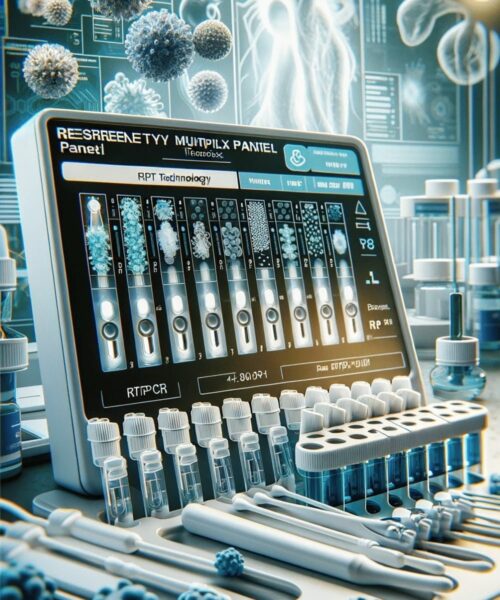

Респіраторна мультиплексна панель (2983) використовується для:

- Швидкого та точного діагностування різних респіраторних інфекцій: Ця панель дає можливість одночасно тестувати на широкий спектр респіраторних вірусів, зокрема SARS-CoV-2 (Covid-19), грипи A та B, респіраторно-синцитіального вірусу та багатьох інших, що є критично важливим для швидкого виявлення та відповідного лікування.

- Підвищення ефективності лікування: Точне та своєчасне виявлення збудника інфекції дозволяє лікарям призначати найбільш ефективне лікування, включаючи антибіотики або противірусні препарати, що зменшує ризик ускладнень та прискорює процес одужання.

- Запобігання поширенню інфекцій: Швидка діагностика допомагає впроваджувати заходи інфекційного контролю для запобігання подальшому розповсюдженню інфекцій серед населення.

- Зменшення часу діагностики порівняно з традиційними методами: У порівнянні з вірусною культурою чи імунофлуоресцентними аналізами, мультиплексний тест набагато швидший, що дозволяє приймати клінічні рішення оперативно.

- Зменшення часу перебування в лікарні та покращення результатів лікування: Завдяки швидкій постановці точного діагнозу, пацієнти можуть отримати відповідне лікування швидше, що призводить до зменшення часу госпіталізації та покращення загальних результатів лікування.

- Інтегрований підхід «зразок-відповідь»: Це забезпечує автоматизацію та інтеграцію всіх процесів – від збору зразка до аналізу, що підвищує точність та надійність результатів.

Респіраторна мультиплексна панель (2983) – це передове рішення для швидкої та точної діагностики різноманітних інфекцій дихальних шляхів. Наша технологія RTPCR забезпечує якісне визначення інфекцій, включаючи:

RTPCR

забезпечує визначення інфекцій, включаючи:

- SARS-Cov2 (Covid19)

- Influenza A & B

- Респіраторно-синцитіальний вірус

- Людський метапневмовірус

- Парагрип

- Риновірус

- Аденовірус

- Мікоплазма пневмонії

- Хламідія пневмонії

- Легіонела пневмофіла

- Кашлюк

- Паракашлюк

- Стрептокок пневмонії

- Гемофільна паличка

Чому обрати панель RTPCR?

Надійність, швидкість, та всебічна точність діагностики

Методи тестування

Використовуючи назофарингеальний мазок, наша панель пропонує найновіші методи RTPCR для ефективного та точного визначення патогенів.

Швидкість та точність:

Наші швидкі мультиплексні молекулярні тести здатні точно виявити широкий спектр вірусних патогенів одночасно, забезпечуючи результати менше ніж за одну годину.

Комплексний підхід:

Наша система “зразок-відповідь” інтегрує вилучення, ампліфікацію та аналіз зразків у закриті процеси, гарантуючи надійність та ефективність.

Зменшення часу діагностики:

Забезпечуємо швидке визначення, зменшуючи час перебування пацієнта у лікарні та покращуючи результати лікування.

Зверніть увагу:

Інфекції дихальних шляхів є третьою за поширеністю причиною смертності та захворюваності у світі. Швидка та точна діагностика є ключовою для ефективного лікування.